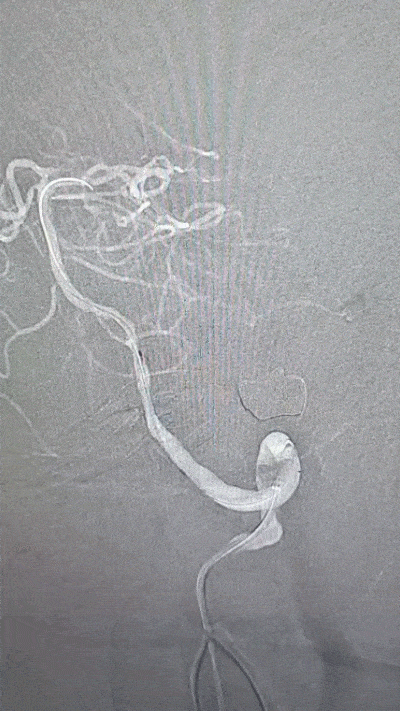

外院DSA(2023.02.09):左侧椎动脉V4段重度狭窄,右侧椎动脉V3段远端闭塞。前循环未见明显异常。